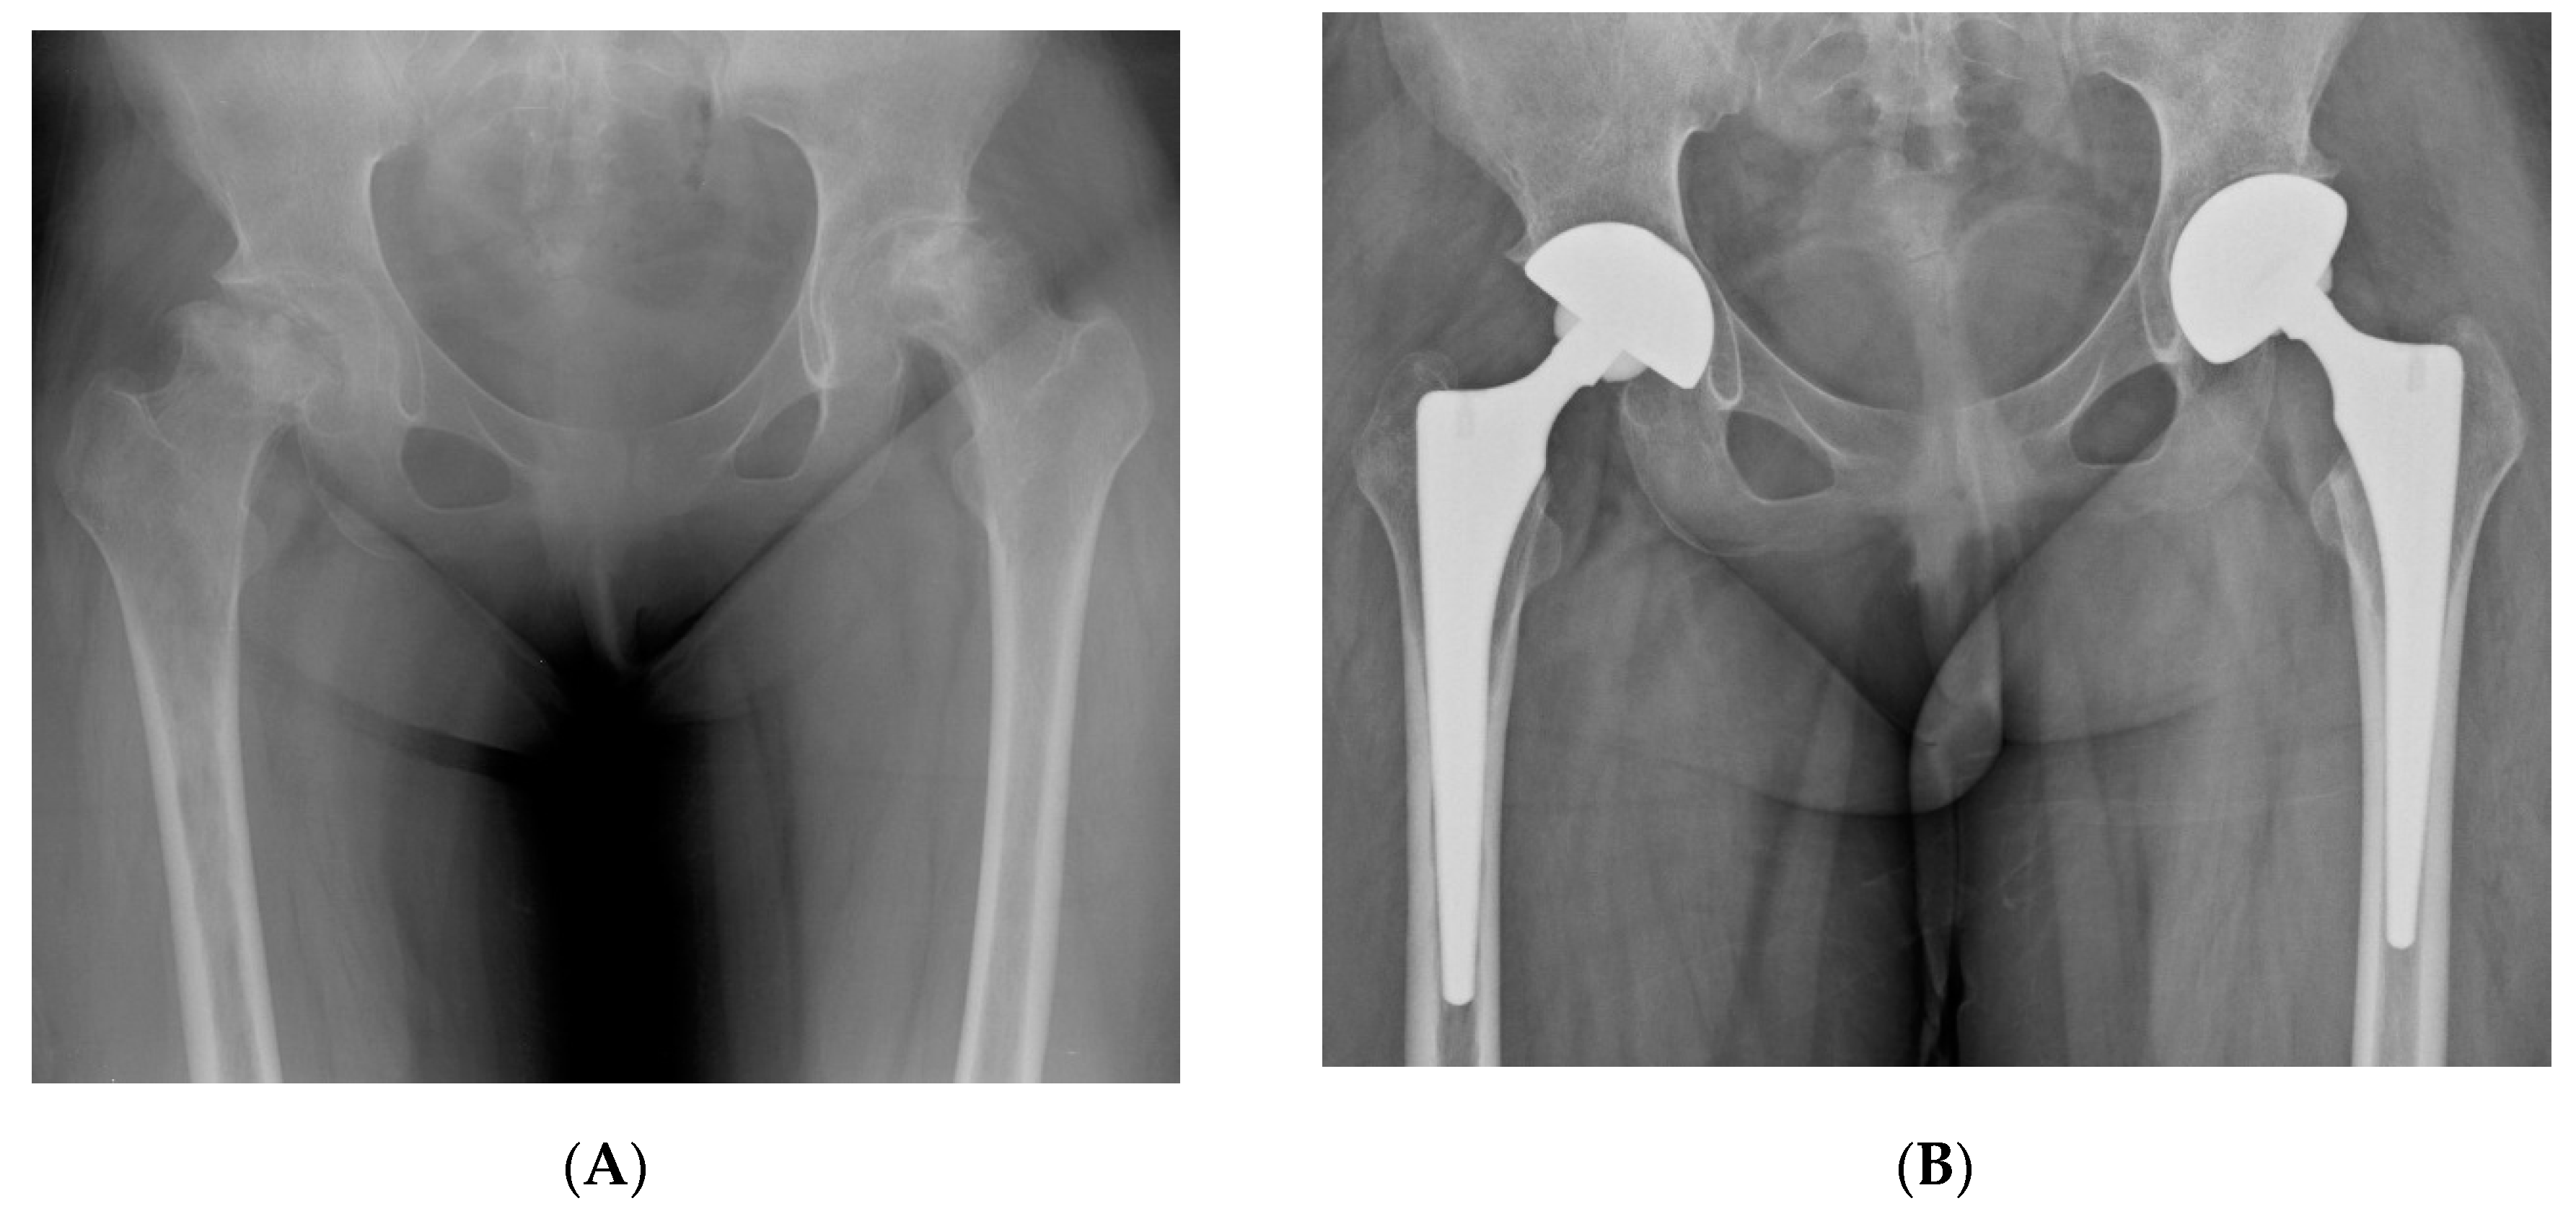

Figure 3.

(A) Preoperative hip radiograph of a 41-year-old man who had undergone surgical removal of meningioma in the right frontal lobe 4 years prior to THA, demonstrating collapsed osteonecrosis of the right femoral head. (B) Five-year postoperative radiograph demonstrating stable implants with Brooker grade 2 heterotopic ossification. The patient had no pain and was satisfied with the outcome.